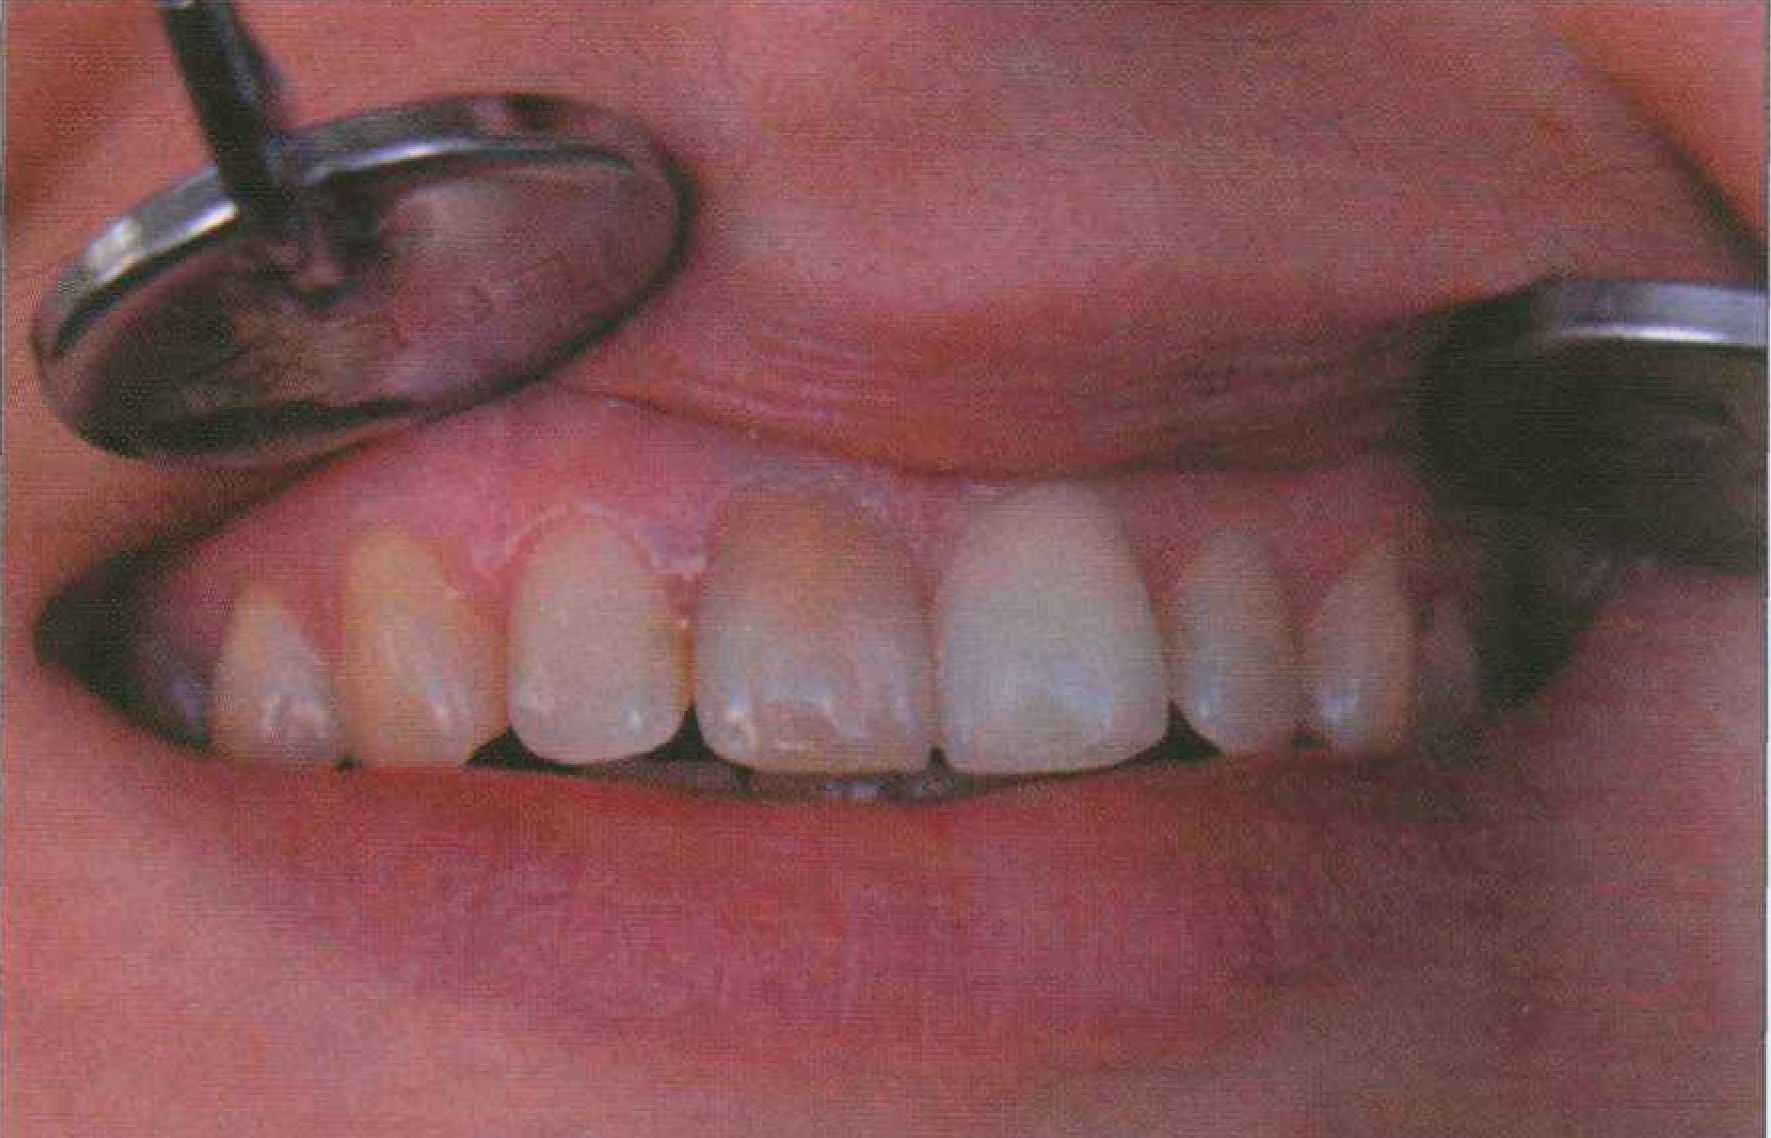

Может наблюдаться пигментация кариозной эмали и дентина пятна с различными оттенками серо-коричневого цвета (рис. 166). В одних случаях пигменты проникают в поверхностный слой эмали, в других случаях твердые ткани окрашиваются на значительную глубину. Может отмечаться также пигментация по периметру пломб, вкладок, вдоль трещин зуба. В ряде случаев появляется также неравномерная диффузная пигментация всей коронки зуба. Экзогенное локальное окрашивание зуба (поверхностное или глубокое) может быть обусловлено металлическими пломбами: медная амальгама придает зеленый оттенок, серебряная — темно-серый, черный. Ряд материалов, ранее использовавшихся в стоматологии, вызывали черную окраску твердых тканей зуба, например ляпис, хромовая кислота. Пигментация эмали и дентина может развиваться как результат проникновения красителей в прижизненные трещины зуба. Степень интенсивности, глубина и площадь окрашивания при этом варьируют в широких пределах, что связано с многообразием локализации, формы, распространенности, степени повреждения твердых тканей (рис. 167). Локальное внешнее или внутреннее нарушение цвета живого зуба может отмечаться как результат травмы в период его формирования. Если травмируется временный зуб, продукты распада клеток крови поступают в ткани зачатка постоянного зуба и могут инкорпорироваться в минерализующийся матрикс эмали. Травма зуба может обусловливать розовую окраску вследствие внутреннего кровоизлияния, когда продукты распада клеток крови из пульпы поступают в дентинные трубочки. Такие зубы приобретают темный коричнево-желтый цвет или непрозрачный желтый оттенок в глубине тканей. Особый случай представляет, так называемый синдром розового зуба, как результат травматического повреждения связочного аппарата. Розовая окраска эмали обусловлена не кровоизлиянием, а прорастанием в зубную полость грануляционной ткани из периодонтальной щели после гибели пульпы в результате разрыва сосудисто-нервного пучка. Грануляционная ткань «разъедает» дентин и спустя годы после травмы начинает просвечиваться через эмаль, придавая ей розовый оттенок. Изменения в пульпе с последующим нарушением цвета зуба могут появляться также, если при ортодонтическом перемещении зубов применяются силы, превышающие физиологическую выносливость периодонтальной связки. В результате этого кровеносные сосуды в пульпе разрываются, и возникает кровотечение. Сначала цвет зуба становится розоватым или красноватым из-за проникших в дентинные канальцы эритроцитов.

Затем последние распадаются, выделяя гемоглобин, который в свою очередь превращается в гемосидерин (темно-желтый пигмент, содержащий железо) и другие пигменты крови. Цвет зуба постепенно превращается в желтый, затем приобретает различные другие оттенки — от коричневого до темно-серого и сине-черного. Тусклый вид эмали, отсутствие живого блеска позволяют заподозрить некроз пульпы. Причины гибели пульпы, как правило, носят экзогенный характер: микробная инвазия со стороны кариозной полости, травматическое повреждение сосудисто-нервного пучка, ретроградный занос инфекции (гематогенный, лимфогенный, по продолжению). Независимо от действующей причины (инфицирование, травма, девитализация) зубы с некротированной пульпой или после удаления пульпы имеют синеватый оттенок или темносерую окраску (рис. 168).